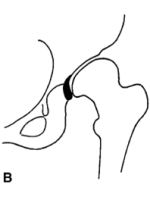

A型先髋患者,股骨头都还在原本髋臼杯内,只有髋臼和股骨头软骨的磨损产生退化性关节炎。

Hartofilakidis B型

B型先髋患者(俗称低脱位先髋),股骨头部分在原本的髋臼内,若股骨头超过50%在原髋臼内叫B1型,低于50%叫B2型。